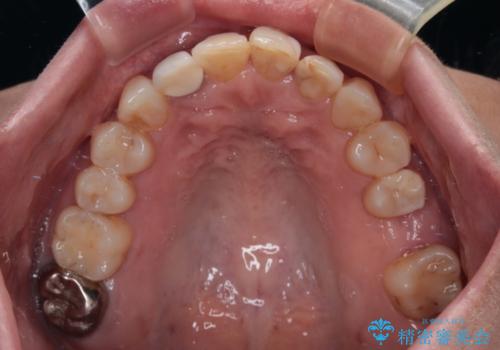

- 前歯のセラミッククラウンの縁が見えることが気になってから、デコボコも気になるようになってきたとのことで来院された患者様です。

デコボコの程度は中等度であったため、インビザライン・モデレートパッケージにて歯列を整えることとしました。

セラミッククラウンの装着されていた前歯と、大きな修復治療の跡がある反対側の歯は、矯正治療後に補綴治療を行うこととしました。

奥歯の欠損はインプラント、ブリッジ、入れ歯のどれにすれば良いかを決められず、仕事が非常にお忙しいこともあり、保留としたまま治療を終えることとなりました。

後戻りのリスクがあるため、なるべく早めに欠損補綴治療を開始する予定です。